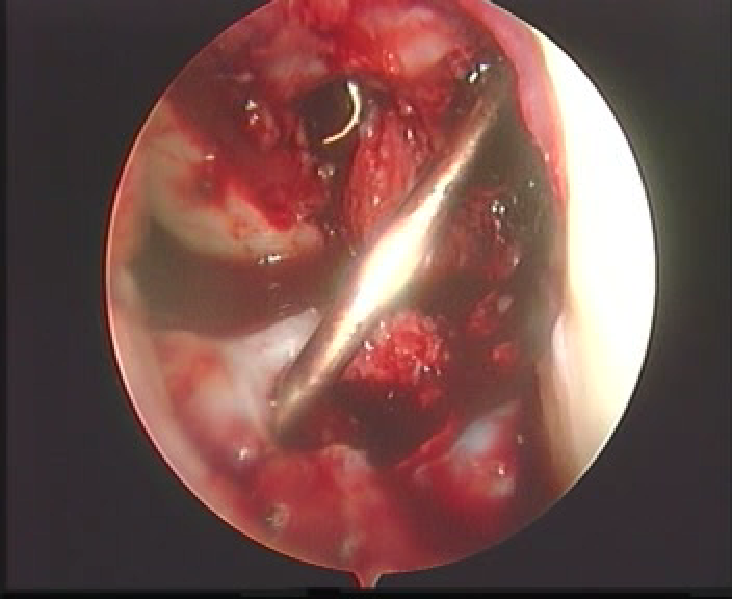

拉进移植物

界面螺钉固定移植物

上胫骨端界面螺钉

拉紧B-P-B,并行后抽屉试验,紧张重建韧带,上胫骨端的界面螺钉,必要时可用门型钉或普通螺丝钉加强固定。

用探钩检查,重建韧带张力良好,前抽屉试验阴性,膝关节屈伸正常。